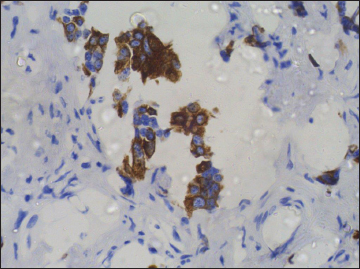

A 52 year-old nonsmoker, alcoholic male patient with spinocerebellar ataxia as comorbidity, presented in November 2016, with a complaint of progressive dysphagia of 2 months duration. Upper gastrointestinal endoscopy showed circumferential growth in lower-third of the esophagus with luminal narrowing. Computed tomography (CT) of thorax showed 13-mm thick circumferential mural thickening involving long segment of the lower esophagus causing marked luminal narrowing [Figure 1]. There was 3.5 cm × 2.5 cm mass in the subcarinal region, compressing esophageal lumen along with the few perigastric nodes [Figure 2]. Positron-emission tomography (PET)-CT showed intense fluoro-deoxy-glucose (FDG) avid thickening in the lower third of esophagus with FDG avid lower paratracheal, subcarinal, and perigastric nodes. Biopsy from the esophagus was done which was suggestive of moderately differentiated squamous-cell carcinoma [Figure 3]. The patient received neoadjuvant chemoradiation with 41.4Gy/23#/5 weeks by 3D-conformal radiation therapy technique along with five cycles of chemotherapy with injection paclitaxel 60 mg/m2 and injection carboplatin area under the curve 2 weekly. There was significant response to the treatment. Subsequently, the patient underwent thoracoscopic esophagectomy with gastric pull with feeding jejunostomy in February 2017. Histopathology showed minimal residual squamous-cell carcinoma of the esophagus with subcarinal node showing features of neuroendocrine tumor [Figure 4]. Subsequently, immunohistochemistry (IHC) was done to confirm the histopathological findings. IHC in esophageal blocks showed strong positivity for CK 5/6 [Figure 5], P63 [Figure 6], and epithelial membrane antigen [Figure 7] in tumor and surface epithelium with Ki67-30% [Figure 8], suggestive of residual small focus of squamous-cell carcinoma. IHC on subcarinal node was negative for CK5/6 and P63, strongly positive for synaptophysin [Figure 9] plus chromogranin [Figure 10], and weekly positive for CK7 [Figure 11], CK20 [Figure 12], and CDX2 [Figure 13]. Ki67 index was 4% [Figure 14], overall suggestive of atypical carcinoid tumor. There was no symptom related to endocrine overactivity or carcinoid syndrome. Follow-up PET-CT was normal, and hence the patient was kept on close follow-up, but at the time of writing the paper, the patient was untraceable.

| Figure 5 Immunohistochemistry on esophageal specimen showing strong positivity for CK5/6